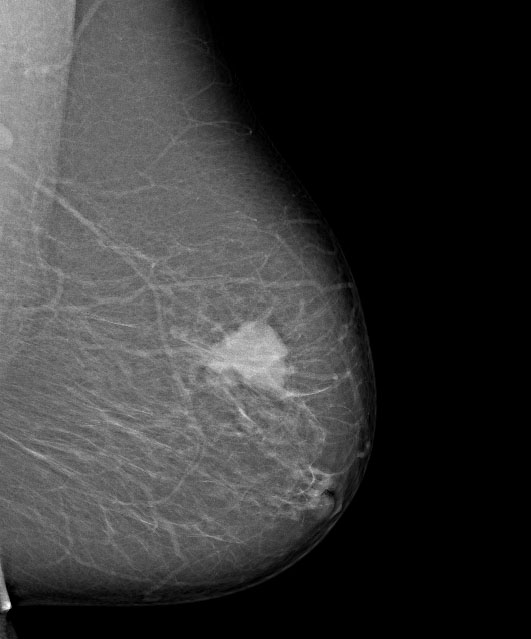

Die Heilungschancen beim Brustkrebs hängen vor allem von der Tumorgröße, dem Lymphknotenbefall und der entsprechenden Primärtherapie ab. Sie besteht in der chirurgischen Behandlung und je nach Situation ggf. einer unterstützenden Strahlen- und/oder Chemo- bzw. Hormontherapie.

Vordringliches medizinisches Ziel der Nachsorgeuntersuchungen ist die frühe Erkennung eines erneuten Knotens in der brusterhaltend operierten Brust, des Zweitkarzinoms in der anderen Brust und des Lokalrezidivs nach Brustentfernung, weil hier noch Heilungsmöglichkeiten bestehen. (hier:Überblick der Nachsorgeuntersuchungen)

Deshalb stehen gründliche klinische Untersuchung, gezielte Anamnese und einige wenige Zusatzuntersuchungen ganz im Vordergrund.